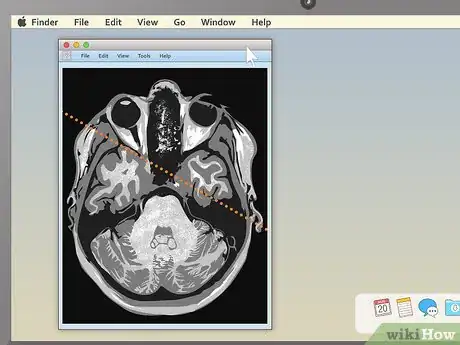

4Use the section-cut line to see where cross-sections are located. If you display a cross-sectional image along with a sagittal or coronal image, you may see a section-cut line on the second image. This will be a straight line running through the image, but it may not be present on all MRIs. If your image does have one, this shows where on the second image the cross section is located. You should be able to move the section cut line toward the center, right or left of the image. This will change the larger layout image to show the body from the new direction of the scan.

- The section-cut line on the layout picture also shows the direction that the image was taken from. For example, if your MRI were a picture of an everyday object, like a tree, the section cut line might show you if the picture was taken from above in a plane, from a second-story window, or from the ground.

5Drag the section-cut line to view new parts of the study. Dragging the section-cut line to a different part of the image allows you to "move around" your MRI images. The image should change your view to the new area automatically.